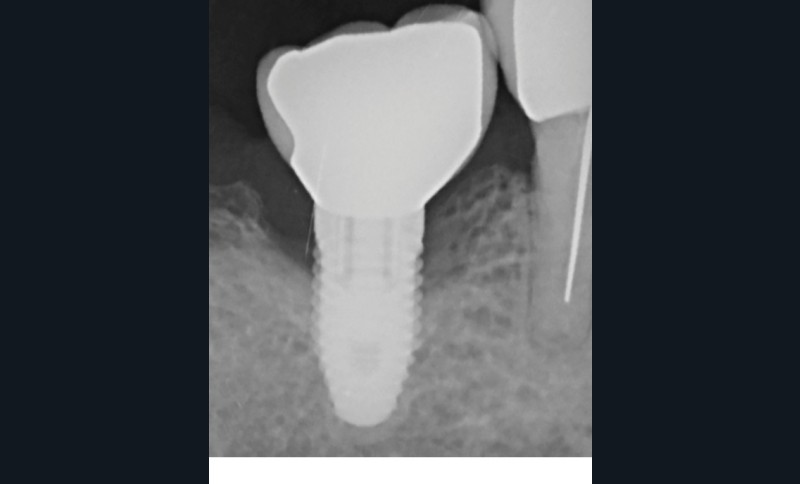

L’implant

- Péri-implantite sur l’implant 47, diagnostiquée en août 2022

- Poches de 6 à 7 mm

- Implant posé en 2017

- Nobel Replace Select RP (4,1 x 10 mm)